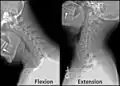

Radiographie de la colonne cervicale en flexion et en extension. Radiographie de la colonne cervicale en flexion et en extension.